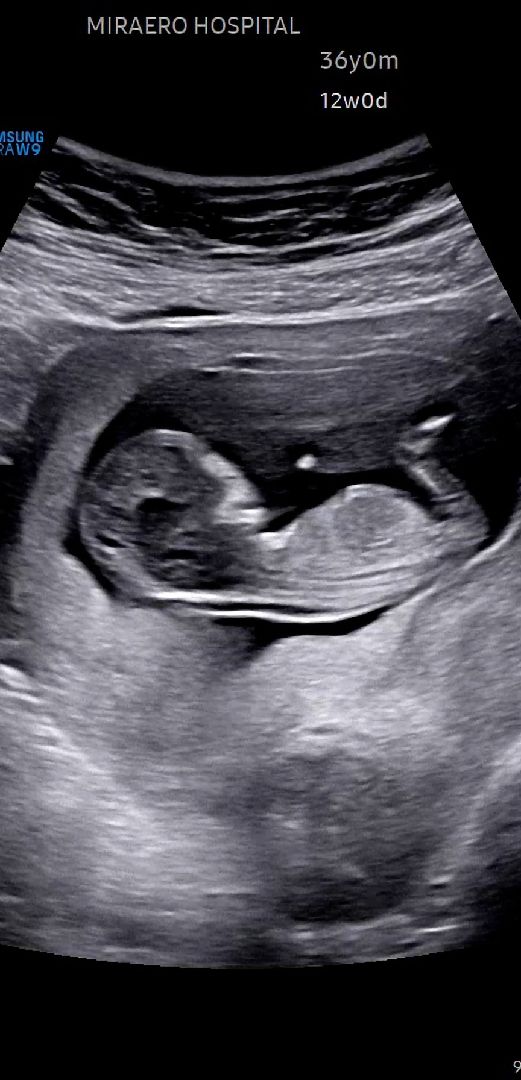

각도법 고수님들 한번만 판독부탁드립니다

아들인지 딸인지 판독부탁드립니다